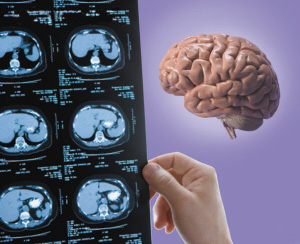

脑瘤CT图片

脑瘤一般可大略分成脑原发性肿瘤及其他部位(如肺、大肠等)转移至脑部的转移性肿瘤。如不适合做磁振造影检查,在影像检查部份,可做电脑断层应可初步判断。但不论是磁振造影或是电脑断层检查,都只能确认脑部是否有构造上的异常(如是否有异常肿块).